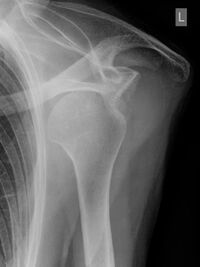

Röntgenbild einer ausgerenkten Schulter

Eine Schulterverrenkung wird häufig durch einen Sturz auf den ausgestreckten Arm oder durch einen starken Zug am Arm ausgelöst. Diese Verletzung treten häufig beim Skifahren, Eishockey, Handball oder Turnen auf.

Bei einer „ausgekugelten“ Schulter steht der Oberarm seitlich vom Körper ab, die normalen Umrisse des Schultergelenks sind verändert, der ausgerenkte Oberarmkopf und die Gelenkpfanne sind tastbar.

Sofortmaßnahmen

Den Arm in einer Schlinge ruhig stellen und Arztin bzw. Arzt aufsuchen. Es sollte nach Möglichkeit kein Versuch unternommen werden, den Arm selbst einzurenken. Denn dabei können Nerven und Gefäße geschädigt werden.

Folgebehandlung

Schnellstmögliche, fachgerechte Einrenkung mit oder ohne Narkose. Anschließend erfolgt eine Ruhigstellung der Schulter für einige Tage oder Wochen. Eine Operation kann bei jungen Sportlern oder schulterbelastenden Sportarten sinnvoll sein.

Vorbeugung

Schutzausrüstung (zB beim Eishockey) und eine gut entwickelte und trainierte Muskulatur im Schulterbereich